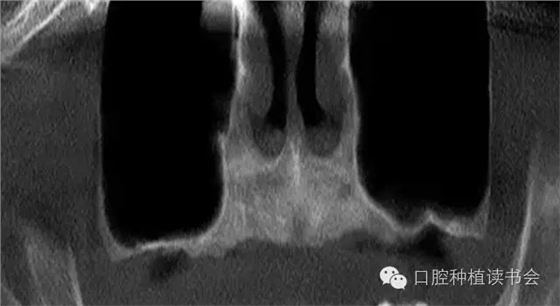

上頜后牙區(qū)牙槽脊吸收的特點(diǎn),主要是垂直高度的吸收。雖然牙槽脊垂直、水平吸收的程度幾乎相當(dāng),但是由于上頜后牙牙槽脊寬度較大,后牙區(qū)經(jīng)常出現(xiàn)圓鈍的、較寬的牙槽骨狀態(tài),臨床表現(xiàn)為剩余牙槽骨高度(Residual Bone Height,RBH)不足。在個(gè)別情況下,由于嚴(yán)重牙周病、根尖病等因素的影響,也會(huì)使牙槽脊水平寬度不足,表現(xiàn)為刃狀牙槽脊。上頜后牙一般為多根牙,當(dāng)牙周病和根尖病到一定程度后,磨牙才開(kāi)始松動(dòng)導(dǎo)致不能保留,又因上頜牙槽骨骨密度較低,在有些病例,牙槽脊重度吸收,RBH甚至不足1mm(圖1)。

▲(圖1)